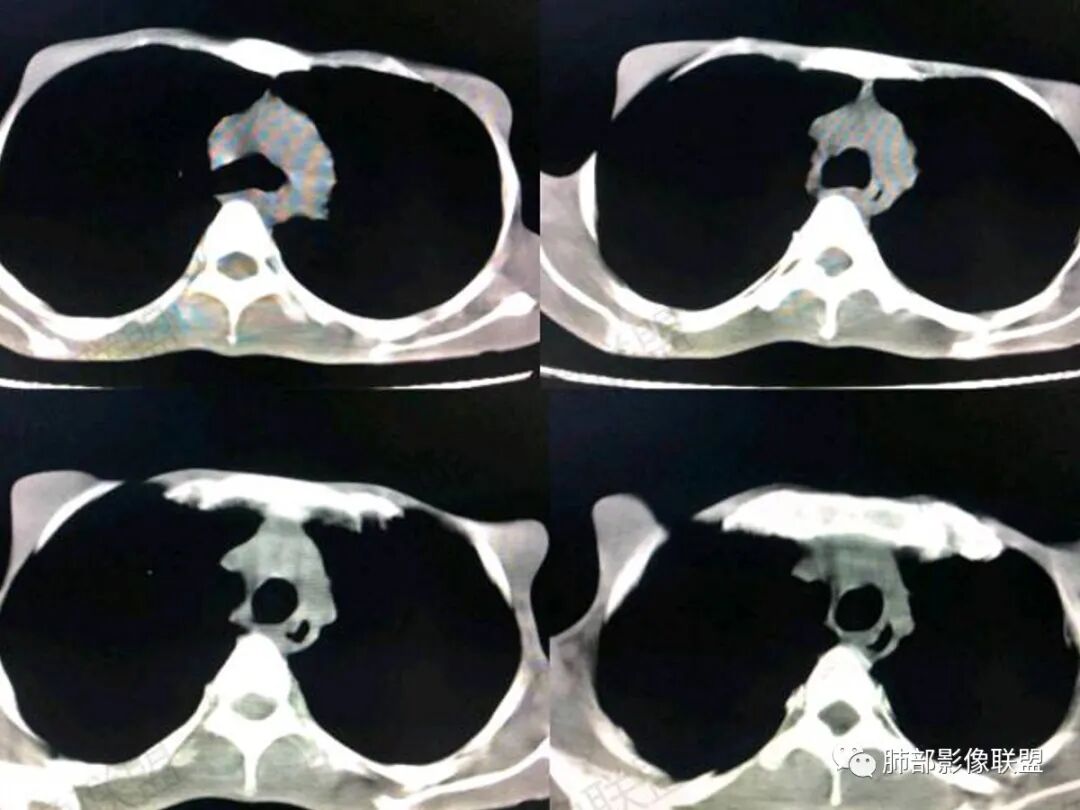

2.双肺多发结节影,实性密度为主,密度偏低且较均匀柔和,没有新旧不等,没有钙化,没有树芽。体型消瘦,皮下少脂肪。

4.肠系膜及腹膜后见增大淋巴结。

1.HIV阳性患者(如此低的CD4计数),高热,皮疹,双肺肺多发结节影(或磨玻璃影),肝脾增大等,首先应当考虑或排除的还是马尔尼菲篮状菌感染。

3.马尔尼菲篮状菌可以出现类似结核的肺部影像学表现。但本患者肺部结节既缺少继发性肺结核特点,也不符合急、慢性血性播散型肺结核表现。

马儿尼菲青霉菌肺部表现具有多样性,可以表现为实质改变、间质改变、纵隔淋巴结肿大、胸膜改变及气管改变。

有文献报道马尔尼菲青霉菌病患者82.7%胸部CT有异常改变,胸部CT表现:45.6%患者肺野斑片状浸润阴影或局限性肺实变,11.9%患者表现为结节影,11.5%患者表现为毛玻璃改变,8.4%患者表现为弥漫性粟粒样病变,5.3%患者表现为结节状肿块影。45.1%患者胸部影像学伴肺门或纵隔淋巴结肿大,23.5%患者伴胸腔积液,8.0%伴空洞病灶。